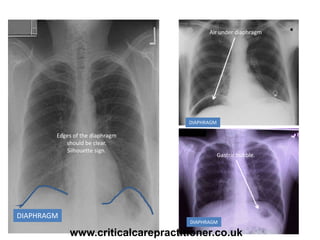

DIAPHRAGM

Edges of the diaphragm

should be clear.

Silhouette sign.

Air under diaphragm

Gastric bubble.